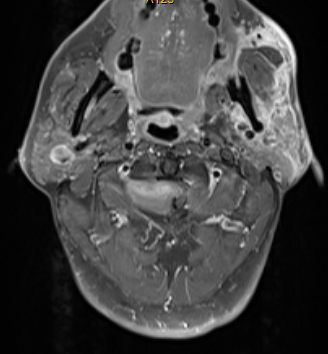

脊柱脊髓外科主任仇继任主任医师对罗先生的病情非常重视,为了查明原因,立即给罗先生完善了相关检查,并对罗先生的症状和体征进行详细分析。各项检查回报后证实了仇继任的考虑,患者第1颈椎椎管内长了一个肿瘤,且位置非常贴近脑干延髓生命中枢,由于特殊解剖生理特点,此处的肿瘤易并发四肢瘫痪和呼吸功能障碍,甚至危及生命。该部位的手术难度大,操作技术要求高,术中处置不当极易导致患者呼吸心跳停止,因此在治疗上存在较大的困难。

为了解决罗先生颈椎上的“定时炸弹”,缓解肢体麻木、行动不便的问题,仇继任及其团队针对罗先生的病情结合术前CT、MRI等影像资料,对治疗方案进行反复讨论和研究,制定了最佳的手术方案——显微镜辅助下精准切除高位颈椎椎管内肿瘤手术。

经过充分的术前准备,仇继任及其团队如期为罗先生进行手术。手术过程中发现肿瘤组织与延髓神经组织粘连紧密,手术难度进一步增大。凭借着精湛而熟练手术技巧及默契的团队配合,仇继任在显微镜下仔细分离肿瘤与脊髓神经组织、精确止血。经过2小时的紧张奋战,手术顺利结束。术后在科室全体医护人员的精心护理下,患者右侧下肢疼痛、麻木症状明显缓解。由于术中未破坏关节突关节,脊柱稳定性得到大部分保留,罗先生术后很快便能起床活动,术后1个星期出院,1个月后随访恢复良好。